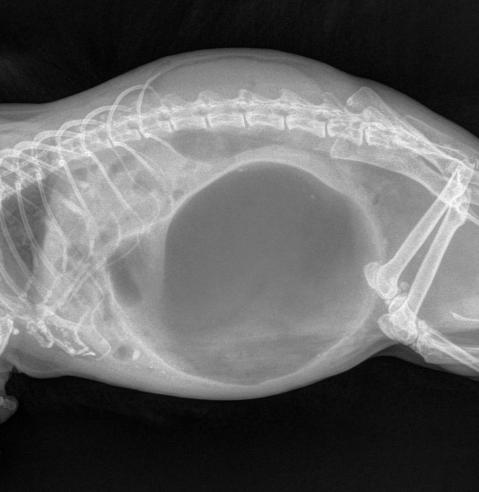

Nadmutí břicha (Tympanie)

Symptomy: Zvířata dýchají zrychleně a povrchně, břicho je výrazně zvětšené a napnuté. Poklepem na stěnu břišní vyvoláme dutý zvuk. Břicho je na dotek tvrdé a velmi bolestivé. Proto vyšetření provádíme zlehka, aby nás činčilka v důsledku bolesti nepokousala. Bobky mají výrazné důlky (po bublinkách) a je jich výrazně méně. Činčila tlačí břicho k zemi. Činčila nejí, hrbí se a pohybuje se s obtížemi.

Zdutí

zdroj: ResearchGate